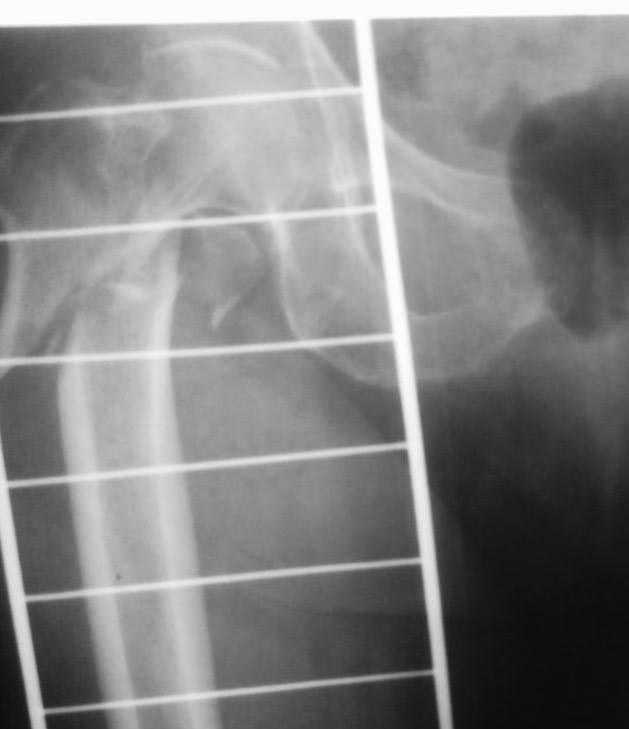

[Ortho] Осторожно! НПП "Имплант", г . Казань

Как-то так